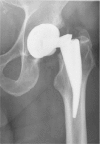

Mechanical surface treatments have a long history in traditional engineering disciplines, such as the automotive or aerospace industries. Today, they are widely applied to metal components to increase the mechanical performance of these. However, their application in the medical field is rather rare. The present study aims to compare the potential of relevant mechanical surface treatments on the high cycle fatigue (R = 0.1 for a maximum of 10 million cycles) performance of a Ti6Al4V standard alloy for orthopedic, spinal, dental and trauma surgical implants: shot peening, deep rolling, ultrasonic shot peening and laser shock peening. Hour-glass shaped Ti6Al4V specimens were treated and analyzed with regard to the material's microstructure, microhardness, residual stress depth profiles and the mechanical behavior during fatigue testing. All treatments introduced substantial compressive residual stresses and exhibited considerable potential for increasing fatigue performance from 10% to 17.2% after laser shock peening compared to non-treated samples. It is assumed that final mechanical surface treatments may also increase fretting wear resistance in the modular connection of total hip and knee replacements.